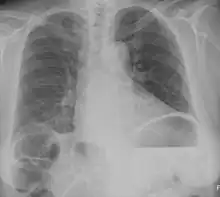

| Chest X-ray showing obvious Chilaiditi's sign, or presence of gas in the right colic angle between the liver and right hemidiaphragm. | |

Chilaiditi syndrome is a rare condition when pain occurs due to transposition of a loop of large intestine (usually transverse colon) in between the diaphragm and the liver, visible on plain abdominal X-ray or chest X-ray.[1]

Normally this causes no symptoms, and this is called Chilaiditi's sign. The sign can be permanently present, or sporadically. This anatomical variant is sometimes mistaken for the more serious condition of having air under the diaphragm (pneumoperitoneum) which is usually an indication of bowel perforation, possibly leading to surgical interventions.